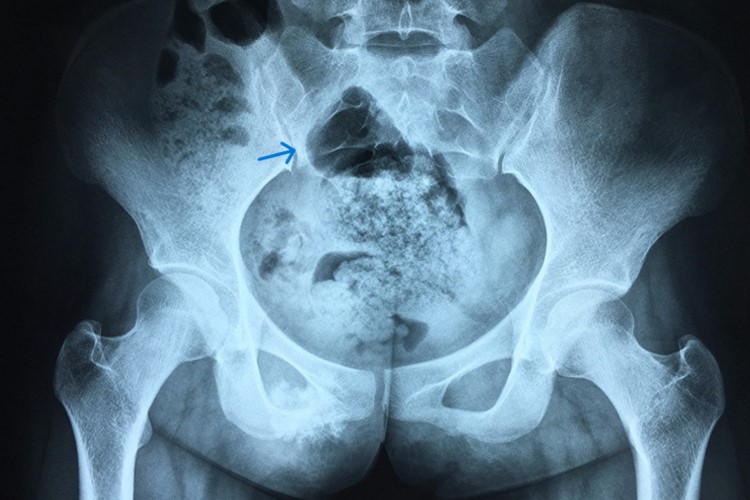

骨癌常可自身体的其他部位扩散或转移到骨内。女性骨癌可出现骨盆、膝盖、上肢等部位,并引起该部位出现明显的疼痛,患处可有异常的肿块,局部肿胀,常伴有疲劳、发热及消瘦等。